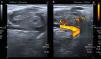

Paciente varo¿n de 53 años, sin antecedentes de interés. Consultó por tumoracio¿n indolora en la parte anterior del antebrazo, sin antecedente traumático. La exploracio¿n confirmó la tumoracio¿n, dura a la palpacio¿n, no desplazable, menor de 1cm. Acudió al gabinete de exploraciones de Reumatología y se practicó una ecografía de partes blandas (Toshiba Aplio®300). Se observó una tumoración redondeada menor de 1cm iso/hipoecogénica en escala de grises, moderadamente delimitada, con un vaso adherido que nutría la lesión (fig. 1). Con Doppler color se observó importante señal, que afecta de manera global a toda la lesión, más intensa en la periferia (figs. 2 y 3). Por signos de sospecha, como la heterogeneidad, la elevada vascularización y la señal Doppler (grado 3) muy importante, se solicitó una RM, que demostró una imagen bien delimitada, redondeada, de 1cm, con hiperseñal en T1, que orientó a una lesión tumoral metastásica (fig. 4).

El caso es útil en la práctica clínica de Reumatología porque: 1) la iconografía permite sospechar la gravedad de una lesión nodular menor de 1cm por su vascularización y heterogeneidad; 2) por destacar la importancia del gabinete de exploraciones de reumatología en el diagnóstico de lesiones tumorales (benignas/malignas) de partes blandas que el reumatólogo no debe eludir; 3) la metástasis cutánea de adenocarcinoma de próstata es muy infrecuente y, en este caso, la ecografía de partes blandas ayudó a orientar el estudio de extensión de la enfermedad neoplásica, y 4) es obligado discriminar las lesiones por su patrón ecográfico y, ante la duda, se debe ampliar el estudio mediante RM4.